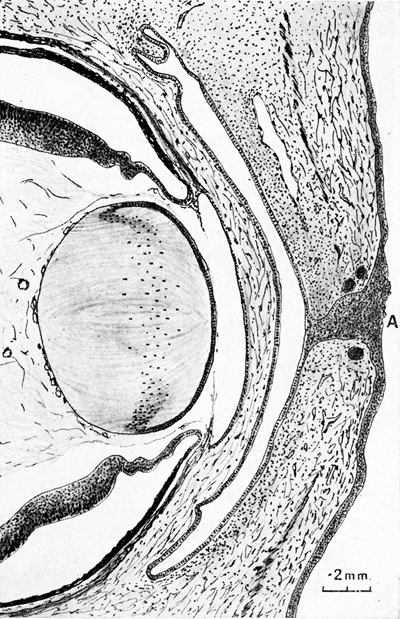

Sección de la porción anterior del ojo a los 48.0mm. de un embrión humano

A- Residuo de la Vesícula Óptica Primaria. B- Borde de la Copa Optica. C- Membrana pupilar. F- Haz de Vitreo de Druault. G- residuo de vaso capsulo-pupilar

Foto tomada de: Ida Mann ; The development of the Human Eye. 1969. Grune & Straton Inc N.Y

Dibujo de corte a través de los párpados todavía fusionados, en un embrión humano de 48 mm